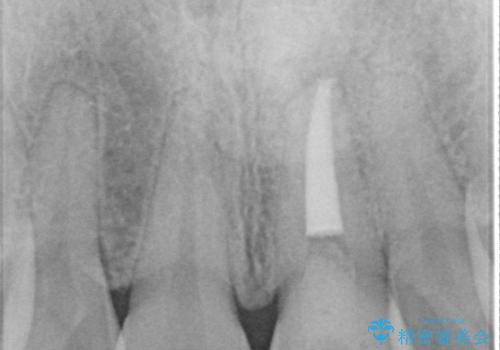

- 前歯が、ポロポロ欠けてくることを主訴で来院された女性です。

以前に根の治療しましたが、最近になって色なども気になり来院されました。

神経の治療をしている歯は、時間と共に色がどんどん変色していきます。

また、神経、血液供給がなくなってしまう影響から歯も脆くなっていってしまうため、歯が割れてしまうリスクもあります。